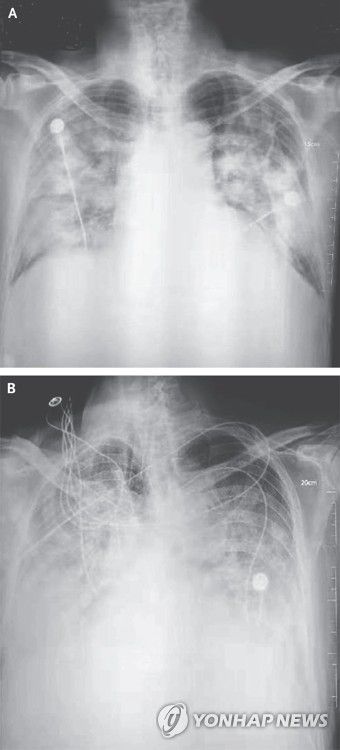

우한 폐렴 환자의 흉부 방사선 사진[NEJM 논문 발췌]

우한 폐렴 환자의 흉부 방사선 사진

[NEJM 논문 발췌]